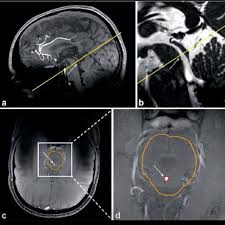

| Cine Phase-Contrast (PC-MRI) | Estudo dinâmico do fluxo do LCR com codificação de velocidade. | VENC ajustado entre 5 e 20 cm/s, plano sagital no aqueduto. |

| 3D T2 SPACE ou CISS/FIESTA | Reconstrução volumétrica do trajeto do LCR. | Alta resolução isotrópica, cortes finos <1 mm. |

- Plano de corte: Sagital mediano como referência principal para planejamento.

- Área de interesse: Todo o trajeto do LCR, incluindo ventrículos, aqueduto cerebral e espaço subaracnóideo.